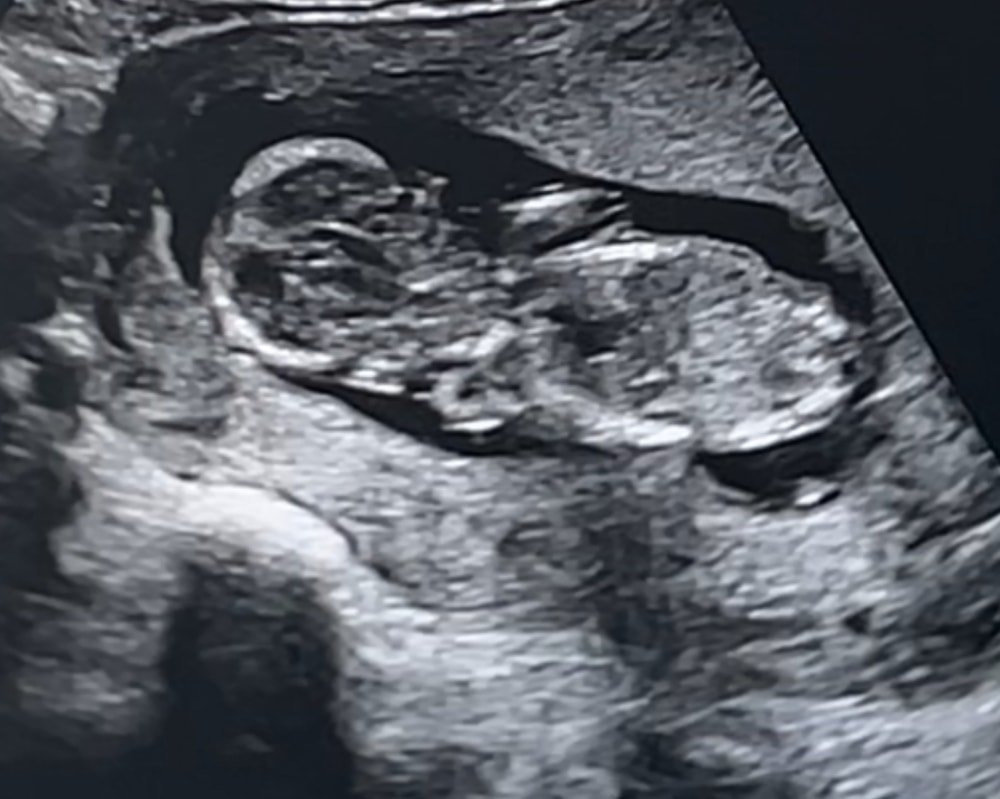

13 недель + 2 дня

на кого похоже? А то я смотрю многие гадают по фото узи …

Посмотрите сами по бугорку,раз у вас есть видео,тут как-то непонятно,то ли пологий бугорок,то ли все-таки вверх пошел))

Светлана, максимум что я увидела на видео. Узи было 1.40 сек 🙈 тут особо не заморачиваються что б все показать))

Даже не знаю это вроде снизу но сбоку как то😅

На этом снимке непонятно, нужно строго в профиль смотреть, а тут малыш чуть развернут.